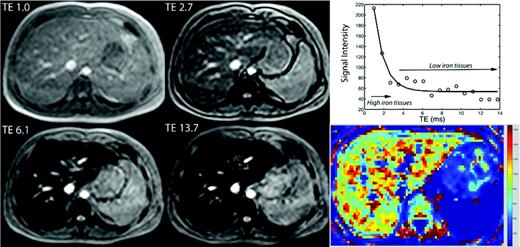

The use of MRI to estimate tissue iron was conceived in the early 1980s, but did not become practical until MRI technology matured 20 years later.6 The general concept is simple.11 MRI machines can generate images at various observation or “echo” times to vary the contrast among different organs. All organs darken with increasing echo time, but those containing iron darken more rapidly (Figure 1). T2* represents the echo time necessary for a tissue to become twice as dark. It may be thought of as a half-life, with small values representing rapid signal loss. Alternatively, image darkening can be expressed by R2*, its rate of darkening. Some investigators prefer to report R2* values rather than T2* values, because R2* is directly proportional to iron concentration12,13 . However, R2* values are simply 1000/T2* and vice versa, making it easily to convert one representation to another.

(Left) Open circles represent liver signal intensity and solid line reflects the R2* fit at different echo times (TE). (Right) A map generated by calculating R2* values for every voxel in the image, with the reported liver iron concentration (LIC) represent the average liver R2* value scaled by a linear equation.12